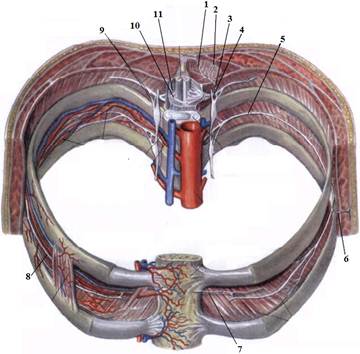

1. Яким номером позначено N. thoracicus?

2. Яким номером позначено N. intercostalis?

3. Яким номером позначено R. cutaneus lateralis?

4. Яким номером позначено R. dorsalis n. thoracici?

5. Яким номером позначено R. cutaneus lateralis r.dorsalis n. thoracici?

6. Яким номером позначено R. cutaneus medialis r.dorsalis n. thoracici?

7. Яким номером позначено R. cutaneus anterior?

8. Яким номером позначено Rr.communicantes n. thoracici?

9. Яким номером позначено Radix dorsalis n. thoracici?

10. Яким номером позначено Radix ventralis n. thoracici?

На таблицях і трупах студенти знаходять судинно-нервового пучка міжребрового проміжку. Далі на трупі розглядають хід і розподіл грудних нервів та ділянки їх інервації, Користуючись таблицями вивчають лімфатичні судини і вузли грудної клітки. На трупі ззаду і справа від грудної аорти знаходять грудну протоку. Визначають її корені хід топографію. На таблицях вивчають корені правої лімфатичної протоки визначають ділянки відпливу до двох головних лімфатичних проток.Викладач консультує студентів по темі заняття, показує незрозумілі деталі будови. В кінці заняття викладач шляхом тестування кінцевого рівня знань та вмінь оцінює роботу кожного студента в академічному журналі.